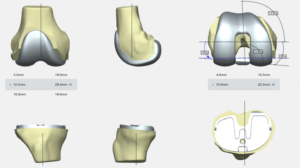

La prothèse comporte donc une pièce fémorale, une pièce tibiale, toutes 2 métalliques, et un insert en plastique (polyéthylène) hautement résistant entre l’implant fémoral et tibial, et parfois un implant en polyéthylène sur la rotule.

Une planification préopératoire après acquisition IRM ou scanner permettra de choisir la taille de la prothèse et son positionnement optimal, ainsi que de fabriquer des guides de coupe sur mesure afin d’obtenir une précision maximale lors de la pose des implants.